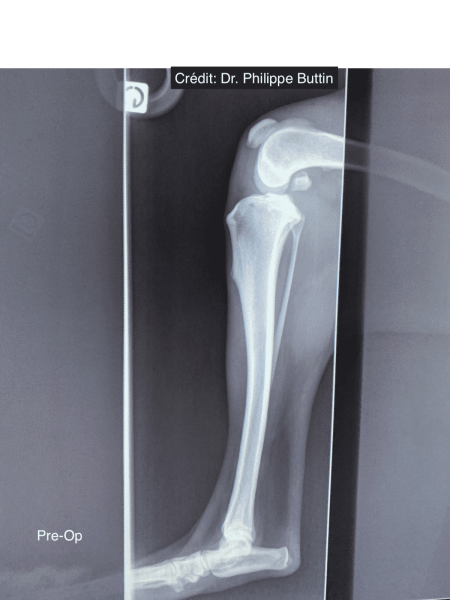

Radiologické snímky